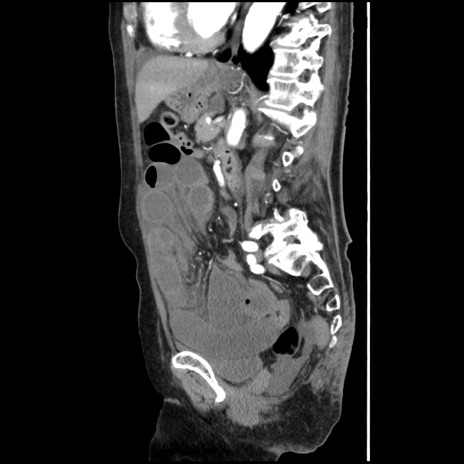

冠状断像